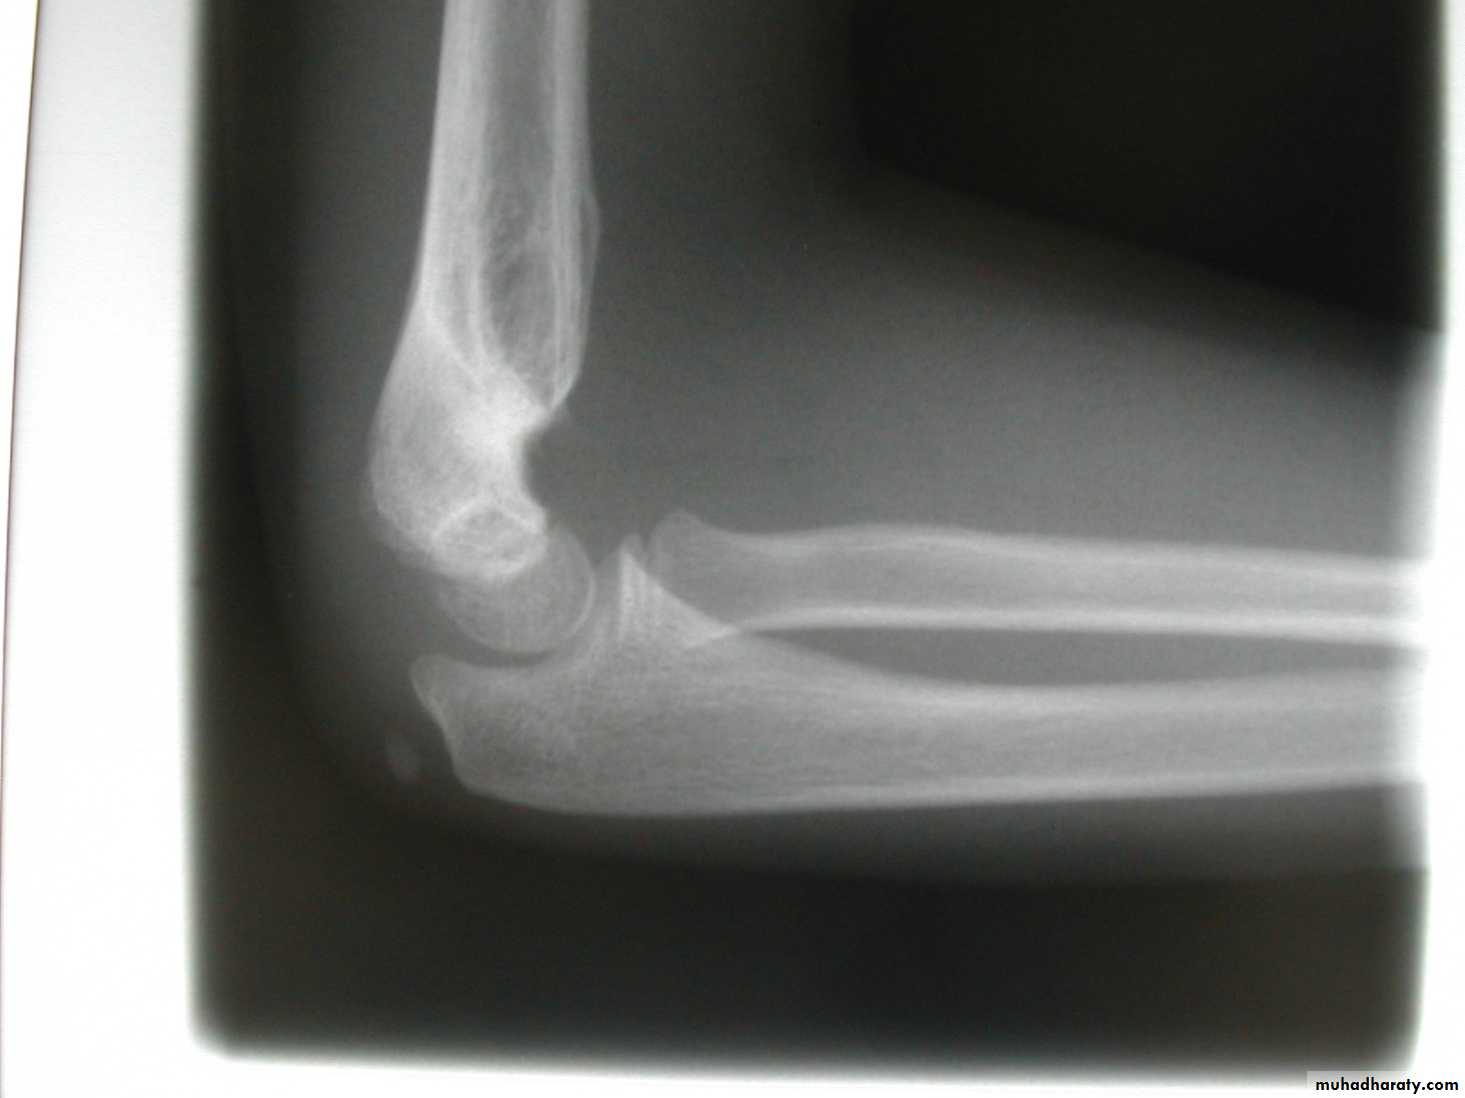

What type of supracondylar fracture

does this patient have?Flex

ionHow do the flexion patterns present?

They present

in the same manner as the extension types.Type I Flexion Injury

This classical Type III pattern

is obviously a flexion injury.With these one needs to be